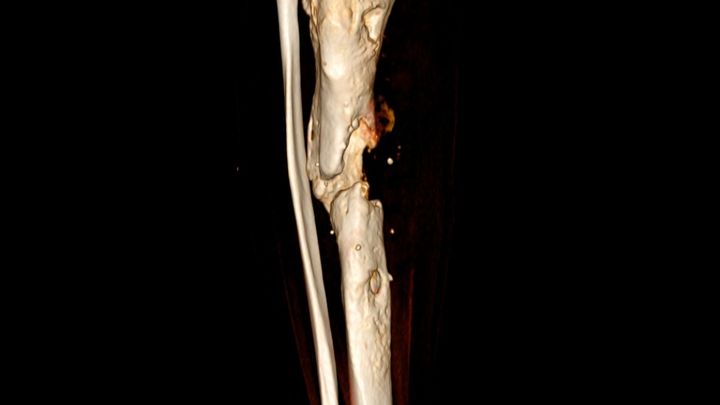

Hace más de un año y medio debido a un accidente practicando cheerleading me rompí la pierna. Todo iba muy bien hasta que comencé con un rechazo de material. He pasado por 3 cirugías para poder volver a caminar pero las cosas se conolicaron... tengo ya una infección en el hueso (osteomielitis) hace poco me dijeron que estaba apunto de perderla por ello (Las imagenes son de mi Xray y mi tomografía). Antes sentía que volaba, y ahora estoy anclado a una cama.